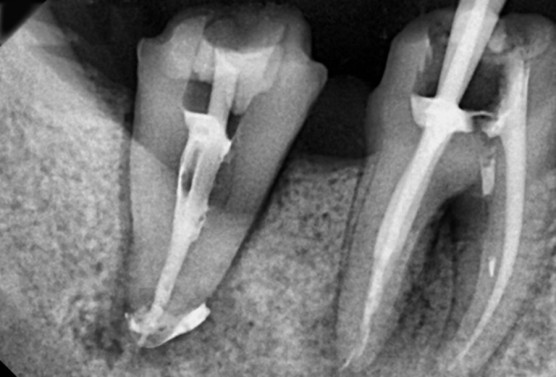

이미지

역시 신비의 약인 MTA를 이용해서 신경치료 마무리를 해준 모습입니다.

약재가 뿌리끝까지 잘 넘어간 걸 확인했습니다. (pumping)

통영신경치료 후에는 보철물을 올려서 보철치료를 통해 마무리를 해주었습니다.